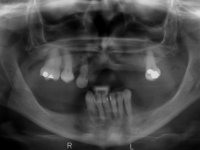

Paciente do sexo feminino, com 52 anos, não fumadora e portadora de uma prótese parcial removível acrílica superior e inferior. No maxilar superior estavam presentes os dentes 1.6/1.5/1.3 e 2.7. O canino apresentava-se com extração indicada. No maxilar inferior estavam presentes os caninos e os incisivos. As próteses removíveis utilizadas não estavam em boas condições. A paciente apresentava uma falta de apoio significativa do lábio superior mas as zonas edentulas do maxilar superior eram compatíveis com a colocação de implantes.

Inicialmente foram confecionadas duas novas próteses removíveis. O dente 1.3 foi extraído quando da colocação das próteses. Feito o estudo imagiológico necessário, foram colocados 4 implantes no maxilar superior. Após 3 meses de osteointegração foi feita a impressão para a confeção de ceras de articulação montadas em placa base aparafusadas aos implantes. Estas ceras foram utilizadas na recolha das relações inter-maxilares e na tentativa de proporcionar apoio ao lábio superior. Foi feita a prova de dentes com estes montados em placas base aparafusadas permitindo uma avaliação estética dinâmica muito interessante. Sendo validada esteticamente pela paciente, esta prova deu origem a uma muralha de silicone que orientou laboratorialmente a confeção da infraestrutura metálica. A infraestrutura metálica com os dentes montados em cera foi provada em boca, permitindo simultaneamente verificar a sua adaptação bem como a estética final. O trabalho final foi colocado em boca sendo acompanhado de instruções rigorosas de técnicas de higiene oral bem como da informação da necessidade de consultas de controlo periódicas.